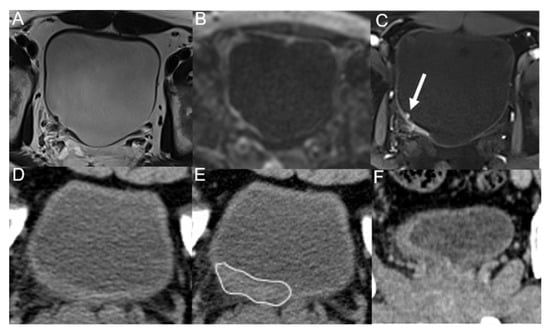

| Morphological Classification | MRI | MDCT |

|---|---|---|

| Nodular masses | 100% (38/38) | 92.1% (35/38) |

| Irregular wall thickening | 90.0% (9/10) | 30.0% (3/10) |

| Smooth wall thickening | 25.0% (2/8) | 0% (0/8) |